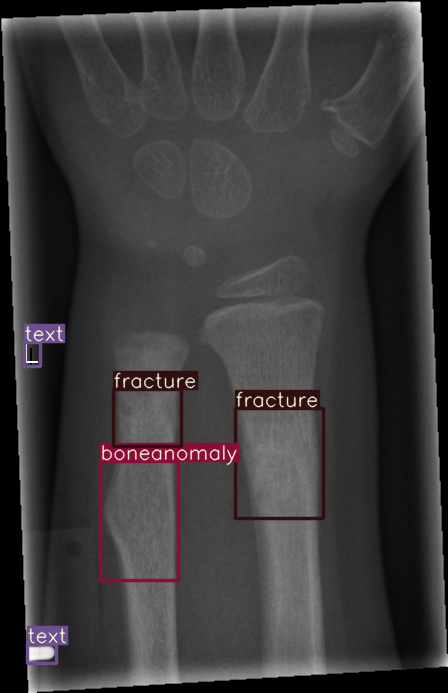

Refer to caption

Figure 4: Bounding box-annotated X-ray images of pediatric wrist trauma from the GRAZPEDWRI-DX dataset [8].

For our experiments, we selected the GRAZPEDWRI-DX images with bounding box annotations in YOLO format, which contains nine classes. Following the data division and augmentation approach outlined by [10], the dataset was randomly divided into 70%percent7070\%70 % training (14,2341423414,23414 , 234 images), 20%percent2020\%20 % validation (4,06540654,0654 , 065 images), and 10%percent1010\%10 % testing (2,02820282,0282 , 028 images) sets. To further augment the training data, the number of images in the training set was doubled by adjusting the contrast and luminance of the images. The label distribution and bounding box statistics are shown in Figure 3. Examples of two training images with bounding box annotations from the GRAZPEDWRI-DX dataset are shown in Figure 4.